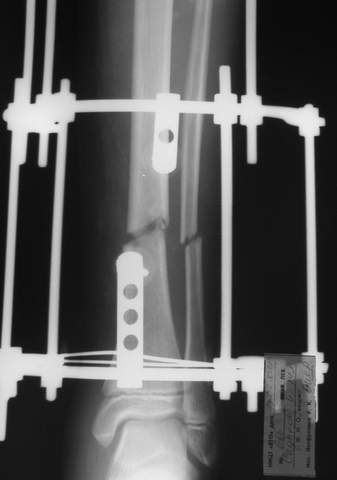

3a

3b

3c

В аттачте № 3 - один из примеров полукольцевого аппарат...

Это уже я баловался.

Итог? Работы больше (по времени и

интраоп "подгонке"), срастается также, а особого преимущества по сравнению с

"чиста" кольцевым (вес, удобство ношения и пр.) - я, по крайней мере,

не нашел.

Теперь не балуюсь.

Может быть зря?